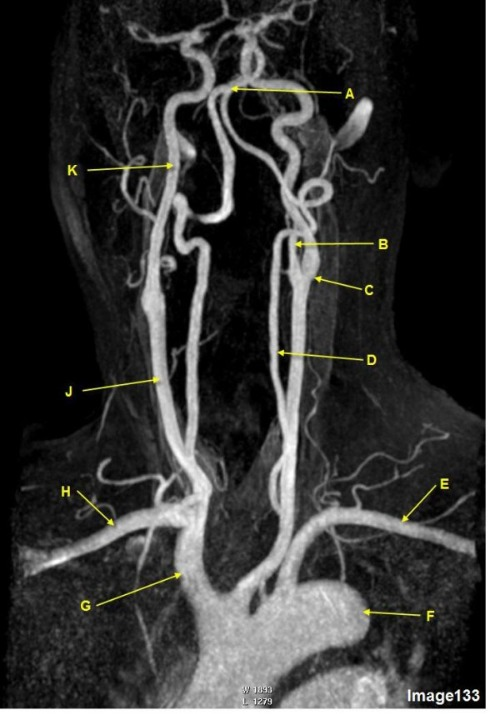

Letter C in Image 133 is pointing to:

B. Common carotid bifurcation

Letter F in Image 133 is pointing to:

D. Thoracic aorta

Letter K in Image 133 is pointing to:

D. Internal carotid artery

Letter E in Image 133 is pointing to:

B. Left subclavian artery

Letter D in Image 133 is pointing to:

A. Vertebral artery